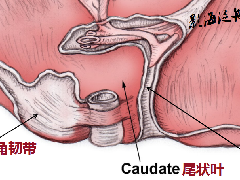

1、假包膜:肝母细胞瘤通常现为巨大的单一肿块,少数为多结节融合。大部分边界清楚, 假包膜形成,病理上为周边受压的正常肝组织。一般胎儿型的包膜较完整, 而胚胎型的欠完整。

▲病例4:胎儿型肝母细胞瘤:男,9个月,肝右叶肝母细胞瘤,CT增强扫描示肿 瘤与周围正常肝组织边界清楚,似有假包膜 (短箭头),其内有裂隙状低密度区,瘤内可见较多粗细不一的肿瘤血管 (长箭头),下腔静脉主要为受压改变 (箭头 )。病理为肝母细胞瘤,胎儿型。